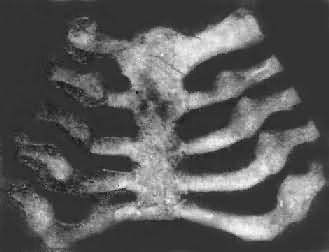

肺的出血性梗死为底靠肺膜、尖指向肺门的锥形病灶(图3-14),暗红色,出血性梗死组织之镜下结构为组织坏死伴有弥漫性出血。

图3-14 肺出血性梗死

肺组织内见一典型的楔形梗死区,梗死区内肺组织出血、坏死(图内呈黑色)